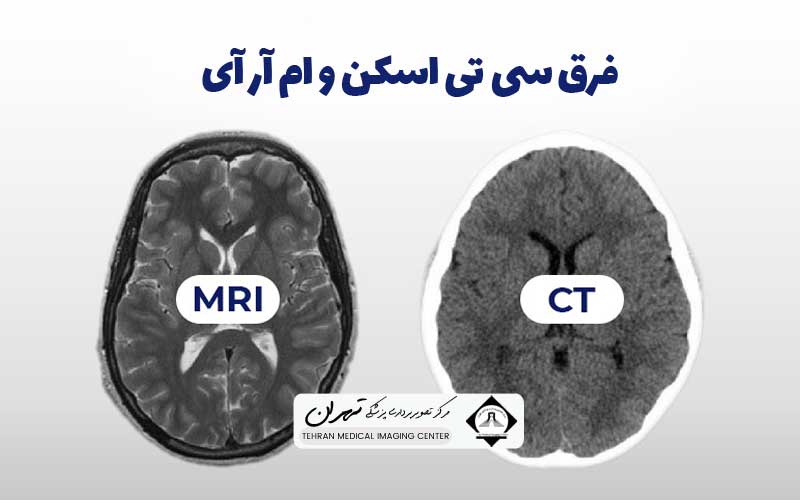

برای بیماران و حتی برخی از متخصصان، درک دقیق فرق سی تی اسکن و ام آر آی و زمان استفاده از هر کدام، میتواند گیجکننده باشد. یکی با استفاده از اشعه ایکس و دیگری با بهرهگیری از میدانهای مغناطیسی قوی و امواج رادیویی کار میکند؛ این تفاوت در فیزیک پایه، منجر به تصاویر با کیفیت و کنتراستهای متفاوتی از بافتهای نرم، استخوانها و عروق میشود. این تفاوتها در نهایت تعیینکننده این هستند که کدام روش برای یک تشخیص بالینی خاص، ارجحیت دارد.

یکی از اساسیترین کاربردهای بالینی که فرق سی تی اسکن و ام آر آی را مشخص میکند، تفاوت در کنتراست و وضوح تصویر از بافتهای مختلف است. سی تی اسکن به دلیل اتکا به تراکم بافت (جذب اشعه ایکس)، در نمایش بافتهای سخت و متراکم مانند استخوانها و عروق خونی کلسیفیه شده، فوقالعاده عمل میکند. تصاویر سی تی اسکن برای تشخیص شکستگیها، ارزیابی ریه و تشخیص خونریزیهای حاد بسیار عالی هستند.

با این حال، سی تی اسکن در تمایز بین انواع مختلف بافتهای نرم (مانند تفاوت بین تومور و بافت مغزی نرمال) کنتراست پایینی دارد. به عبارت دیگر، بافتهای نرم با تراکم مشابه، رنگهای خاکستری یکسانی در تصویر سی تی اسکن پیدا میکنند و تشخیص مرز بین آنها دشوار میشود.

در نقطه مقابل، ام آر آی در تولید تصاویر با کنتراست عالی از بافتهای نرم بیرقیب است. به دلیل حساسیت بالا به محتوای آب و چربی بافتها، ام آر آی میتواند تفاوتهای ظریف در ترکیب شیمیایی بافتها را نشان دهد. این قابلیت باعث میشود که ام آر آی روش انتخابی برای تصویربرداری از سیستم عصبی مرکزی (مغز و نخاع)، مفاصل، رباطها، تاندونها و برخی تومورهای بافت نرم باشد.

به طور خلاصه، درک فرق سی تی اسکن و ام آر آی از منظر کیفیت تصویر به ما میگوید که برای دیدن ساختار استخوانی و ریه، سی تی اسکن و برای دیدن جزئیات بافت نرم و آسیبهای مغزی، ام آر آی ارجحیت دارد. پزشک با توجه به اندام مورد نظر، بهترین روش را برای دستیابی به اطلاعات تشخیصی با بالاترین وضوح انتخاب میکند.

از دیدگاه متخصصان، فیلم و کیفیت نهایی تصاویر تولید شده توسط این دو دستگاه، جایی است که فرق سی تی اسکن و ام آر آی به طور واضح آشکار میشود. سی تی اسکن تصاویری تولید میکند که وضوح فضایی (Spatial Resolution) بسیار بالایی دارند و برای نمایش جزئیات کوچک استخوانی، گرههای ریوی و مرزهای هوایی عالی هستند.

فیلم سی تی اسکن، ساختارهای مختلف را عمدتاً در مقیاسهای خاکستری بر اساس چگالی نشان میدهد؛ استخوانها سفید روشن، بافت نرم طیفهای خاکستری و هوا سیاه است. با این حال، وضوح کنتراست (Contrast Resolution) آن برای تمایز بافتهای نرم مشابه، پایین است و این فرق سی تی اسکن و ام آر آی را در کیفیت خروجی نشان میدهد.

ام آر آی، تصاویری با وضوح کنتراست فوقالعاده بالا تولید میکند. فیلم ام آر آی میتواند تفاوتهای ظریف در محتوای آب و چربی بافتها را به صورت رنگهای خاکستری متفاوت نشان دهد، که این امر برای تشخیص پلاکهای کوچک در مغز (مانند بیماری ام اس) یا آسیبهای مینیسک زانو بسیار مهم است. تصاویر ام آر آی اغلب به چندین سکانس مختلف (مانند T1 و T2) تقسیم میشوند که هر کدام اطلاعات متفاوتی در مورد بافتها (مانند وجود آب، خون یا چربی) ارائه میدهند.

به طور خلاصه، برای یک متخصص، فرق سی تی اسکن و ام آر آی در نوع اطلاعاتی است که هر فیلم ارائه میدهد: سی تی اسکن بر ساختار سفت و تراکم متمرکز است، در حالی که ام آر آی بر ترکیب بافت نرم و تغییرات پاتولوژیک ظریفتر متمرکز است.